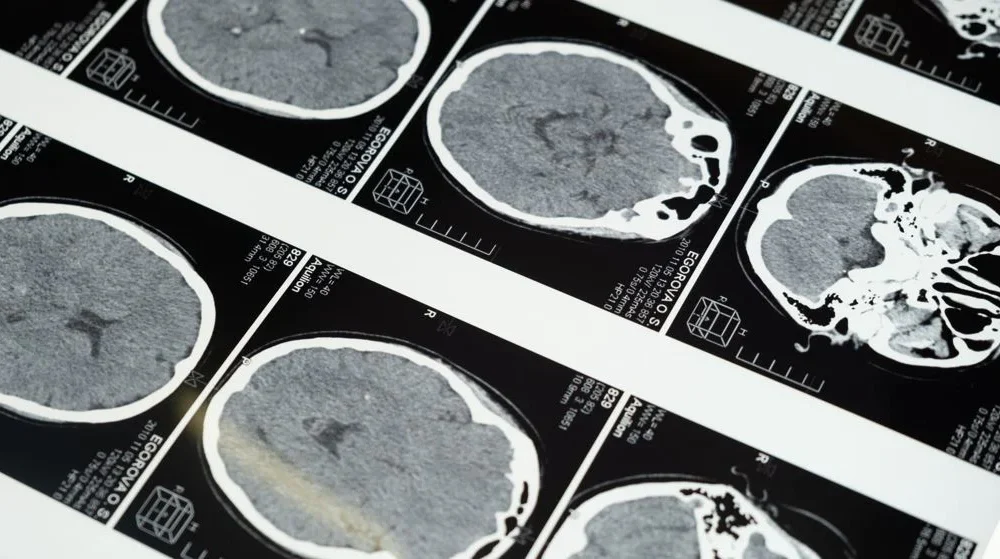

The study cohort consisted of 22 individuals with moderate or severe sinus inflammation, matched with a control group of 22 individuals without sinus inflammation. Utilizing functional MRI scans and cognitive/behavioural measurements, the researchers made several noteworthy observations. The study subjects with sinus inflammation exhibited decreased functional connectivity in the frontoparietal network, responsible for executive function and problem-solving. Additionally, they displayed increased functional connectivity in nodes of the default-mode network, which influences self-reference and mind-wandering. Conversely, decreased functional connectivity was observed in the salience network, involved in detecting and integrating external stimuli and social behaviour. The severity of sinus inflammation correlated with the magnitude of these brain-activity differences.

Dr. Kristina Simonyan, a study co-author, emphasizes that while individuals with sinus inflammation did not show signs of cognitive impairment, their brain scans revealed subtle alterations in communication between brain regions responsible for attention, focus, and sleep. These findings suggest that the subjective experiences of individuals with sinus inflammation, such as attention decline and sleep disturbances, may be associated with these subtle changes in brain activity.